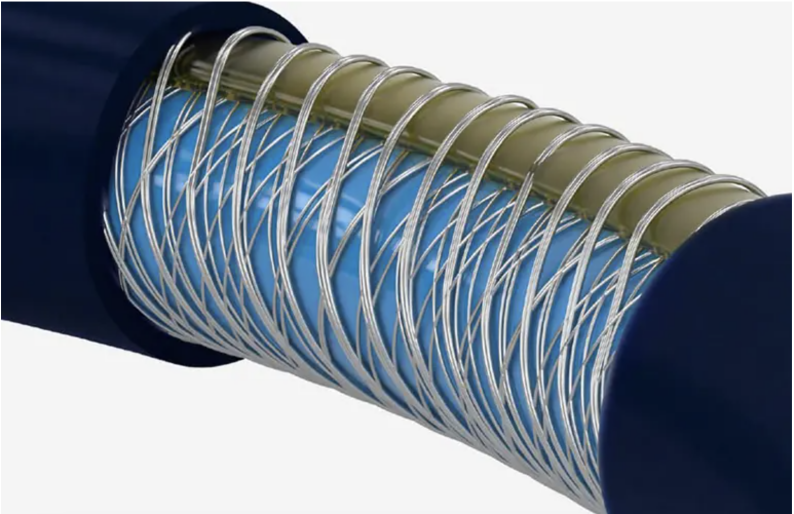

在这个产品的创新设计中,导管内腔越大,效果越好。关于抽吸的设计创新中,内腔的最大化,包括使用新的编织结构,材料,以及外层的可变硬度热塑料,其目的就是防止内径大后,导管整体性能的损失。

在一些手术中,也设置了“抽吸导管+支架”“抽吸导管+BGC”(封堵)的组合方式。其中BGC的设计原理往往会导致其偏硬,穿主动脉弓难一些。于是一种新的偏心设计,则很好的满足了它,实现了更好的可追踪性。